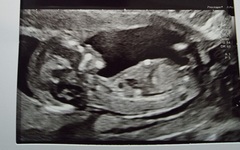

Hi All Does any one have experience with the Nub Theory? I have posted my scans on FB Groups and also paid £10 to the nub Techs. All say boy so I'm guessing I'm having another little boy. But is it accurate? Can I assume I am having a baby boy from this or is it just a total guess? I've already bought a few blue cardigans as the accuracy rate on the website etc is super high! Lol. The baby does have a super "boy" nub from other photos I've seen. Anyone used them and they have been correct or incorrect for you?? Thanks!